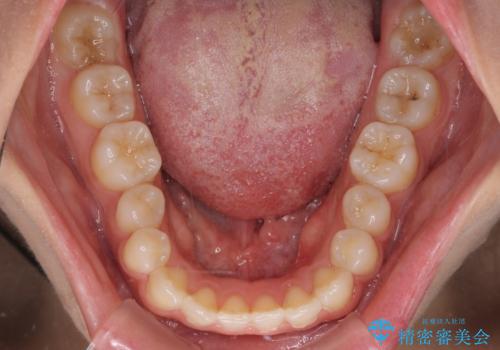

インビザラインを用いた上顎の部分矯正

- 上顎前歯の叢生を気にして来院された患者様です。

下顎前歯や上下奥歯の咬み合わせには殆ど問題がないため、上顎前歯のみを矯正する治療を提案しました。

ワイヤー装置でもインビザラインでも可能でしたが、前歯のみをきれいに排列するのであればインビザラインの方が仕上がりが良いので、インビザライン・ライトにて治療を行うこととしました。